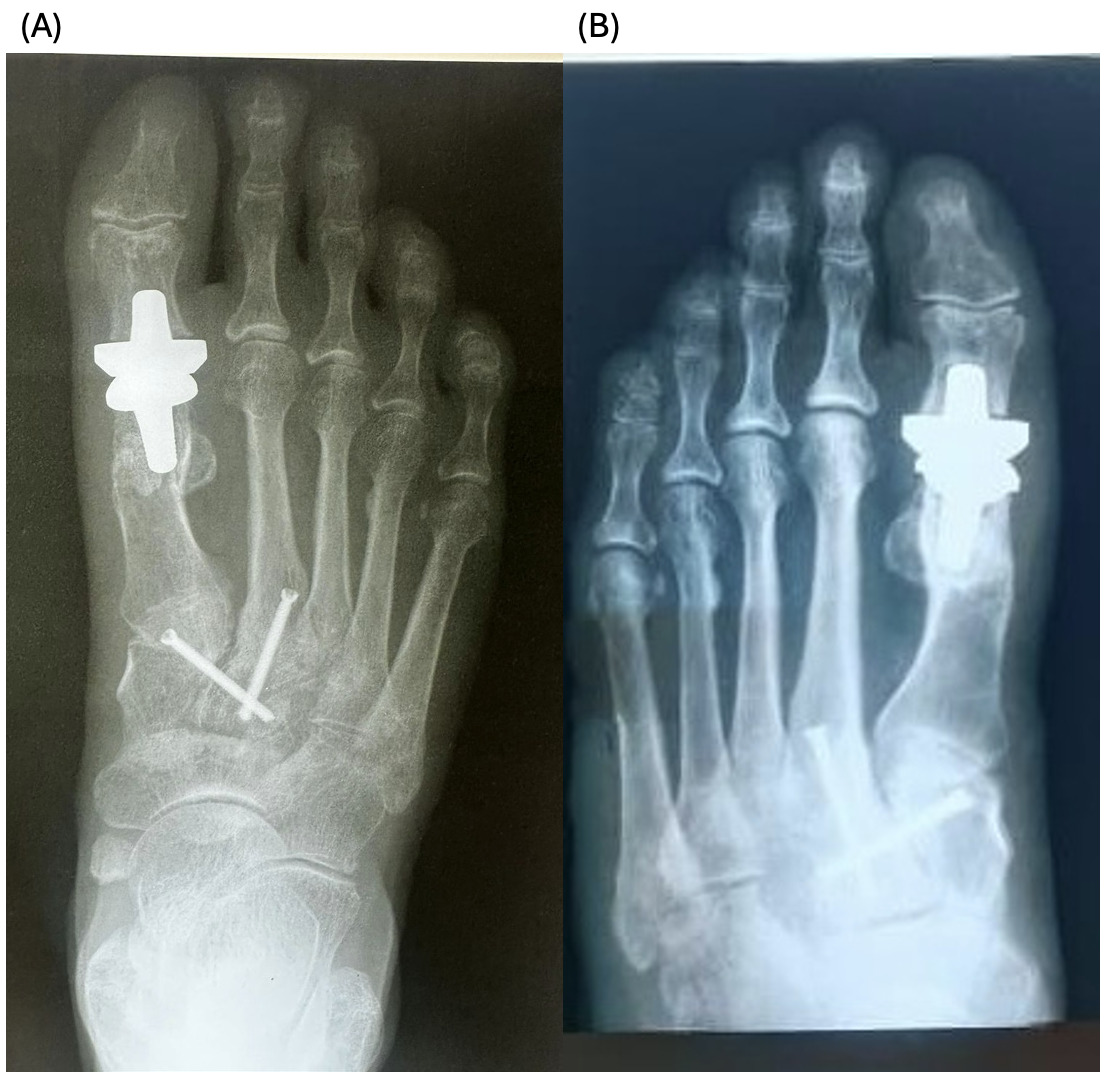

The patients had undergone radiographic evaluation of the MTP joint before the surgery, right after surgery, and 2 and 6 months after surgery (Figures 4-9). The radiographic imaging after the surgery confirmed the correct positioning and alignment. At the follow-up, the radiographic images were done to analyze the early healing process, to observe if there were any signs of implant loosening. 2 months after the surgery, no patient had periprosthetic radiolucencies, no stress-related changes. 6 months after surgery, no osteolysis, no migration of the implant.

This case series demonstrates successful short-term results following total first metatarsophalangeal (MTP) joint replacement using ceramic implants in patients with hallux rigidus. All three patients presented significant improvement in AOFAS scores within 2 months postoperatively, with preserved improvement at 6 months. Notably, Patient C, who had the lowest preoperative score (27/100), achieved the greatest relative improvement, reaching 92/100 at 2 months and 89/100 at 6 months. These functional outcomes were confirmed by physical examination findings, with clear improvements in joint alignment and reduction in deformity (Figure 1-3, (B, C)). Moreover, radiographic imaging revealed no signs of complications such as implant loosening, migration or stress-related changes.

._patient_a__immediate_postoperative_radiograph_(b).png)

._patient_a__6-month_follow-up_radiograph_(b).png)

._patient_b__immediate_postoperative_radiograph_(b).png)

._patient_b__6-month_follow-up_radiograph_(b).png)